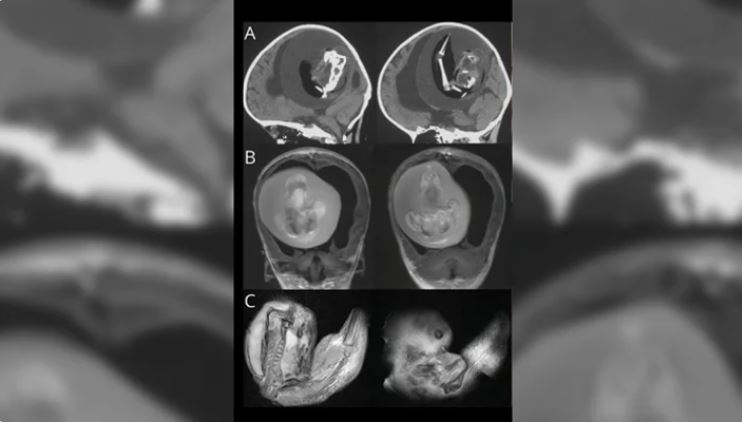

اكتشاف جنين غير مكتمل في جمجمة طفلة عمرها عام

عمون - كشف تقرير حالة طبية جديد عن حالة نادرة ومأساوية لطفلة تبلغ من العمر عاما واحدا في الصين، حيث وُلِدت بجنين غير مكتمل داخل جمجمتها.

الطفلة، التي كانت تعاني من تورم حاد في الرأس وتأخر في النمو، أجريت لها عملية جراحية من قبل جراحي الأعصاب لإزالة الكتلة.

للأسف، توفيت الطفلة في غضون أسبوعين بسبب الأضرار الشديدة التي لحقت بدماغها، والتي جعلتها غير قادرة على البقاء على قيد الحياة.

حالات مثل هذه، المعروفة علميا باسم "جنين داخل الجنين" (fetus in fetu)، تحدث بنسبة نادرة جداً، حيث تؤثر على حوالي واحد من كل 500 ألف ولادة.

وتم تسجيل حدوث حوالي 18 حالة فقط داخل الجمجمة حتى الآن.

الأطباء لم يفهموا بعد الأسباب الدقيقة لحدوث هذه الظاهرة، ولكنهم يعتقدون أنها تحدث خلال التطور في الرحم، عندما لا ينفصل التوأم المتطابق تماما، مما يؤدي إلى تضافرهما في تكوين واحد.

عمليا، يتم استقرار الأنسجة الجنينية الممتصة في البطن في 80% من الحالات، مما يسمح للأطباء بإزالتها بنجاح. وفي بعض الأحيان، يتم اكتشاف الظاهرة في مناطق مثل فم الطفل أو كيس الصفن أو العصعص.

بالرغم من ذلك، فإن حالات الجنين داخل الجنين التي تحدث في الرأس تكون دائما مميتة بنسبة تقارب 100%، كما ورد في التقرير الذي نشره أطباء من مستشفى جامعة بكين الدولي.